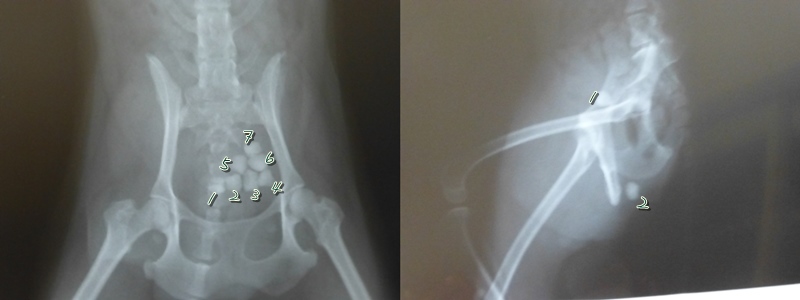

埼玉に引っ越して事情を説明、最初のレントゲンで石7個見つかる。

この4年間(実際は1年半)の間に石が立て続けに5つ出る。

直径5mm程度といってもかなりの存在感。

28日(火)再度、連れて行きレントゲン。石が尿管に詰まっていると判明。

左が今の病院最初にで取ってもらったレントゲン。

右が今日撮ったレントゲン、石がかなり下まで下ってきています。